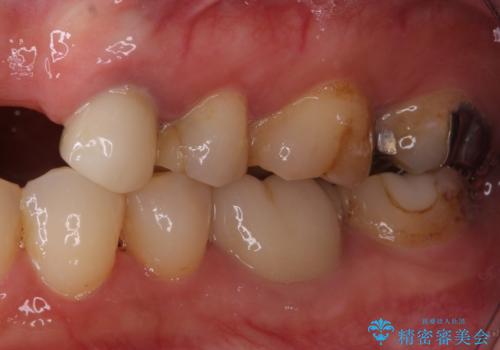

- 他院で矯正治療を終えたものの、むし歯や欠損部の治療が進められないとのことで来院された患者様です。

欠損部や、銀歯やむし歯の大きな歯はセラミッククラウンやブリッジに、小さいむし歯はセラミックインレーにて治療を行うこととしました。